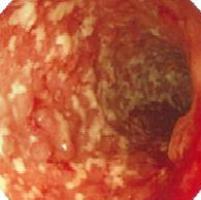

<内視鏡検査>

粘膜は発赤、腫脹し、血管透見像は消失します。

また、多発性のびらん、潰瘍あるいは偽ポリポーシスなどがみられます。

生検で、粘膜に限局する炎症所見、陰窩膿瘍などが認められたら本症を強く疑います。